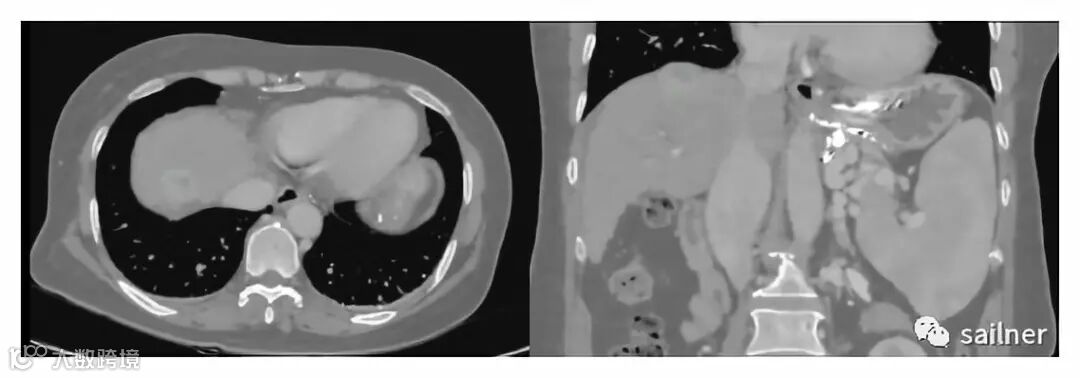

CT影像

病例危害性:肝移植要求供体肝脏重量必须大于等于受体体重的1%,所以,对于这样的精准的手术,供肝切多大、呈什么形状,两块肝脏血管、胆管如何精确吻合,对供体的肝脏切法就十分讲究,从肝中静脉的左沿还是右沿切,切口距离血管分叉处的距离都很重要,以防止吻合口的狭窄等等,都有着极高的要求。为了制定周密计划,确保手术成功,杨教授想到了运用3D打印技术。

术前:通过CT影像 → 计算机建模 → 3D打印,彩色多材料1:1打印患者肝脏实物模型,真实直观的再现病灶部位,能精确评估病变范围与临近脏器组织的三维空间关系,从而制定详细的手术规划,确定手术方案。该模型在术前交付给医生,在手术前进行手术模拟。